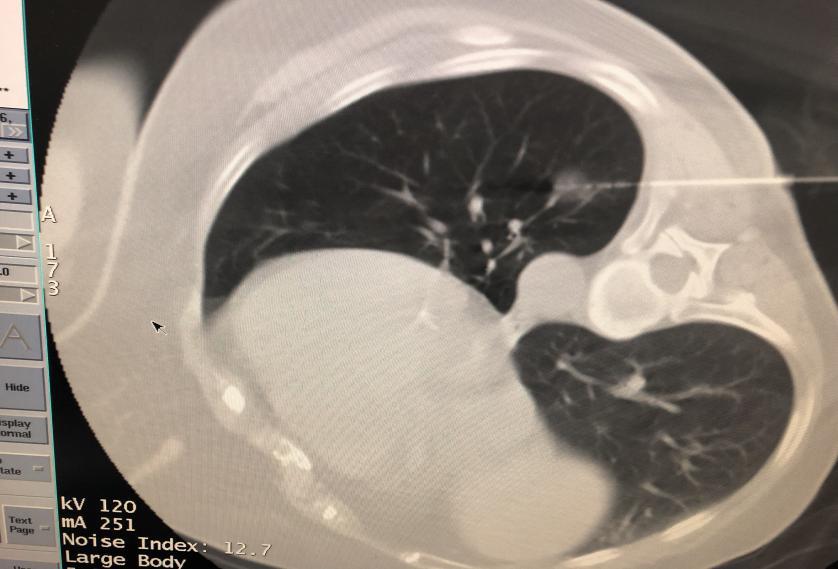

微波消融术是一种微创手术,即在CT定位下,将一种特殊的微波消融针经过皮肤穿刺至肺肿瘤内,通过发射微波,几分钟即可“烧死”肿瘤,创伤小,局部麻醉即可完成。